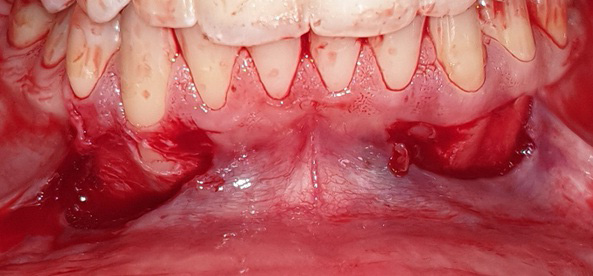

The graft was positioned in its bed and held pressed for 2 min for initial stability. At one side, the graft was stabilized using 0/5 nylon sutures (interrupted sutures to the papilla and a sling suture were placed to adapt the graft intimately to the root and periosteal bed),25 while at the other side, FGG was stabilized with the tissue adhesive (Figure 2, Figure 3, Figure 4).

As to the healing index, there were no significant differences between the 2 sites after 1 week, 2 weeks, 1 month, and 2 months. However, the healing process was completed 1 month postoperatively in the tissue adhesive group, whereas in the suture group, it lasted up to 2 months (Table 5) (Figure 5, Figure 6, Figure 7).